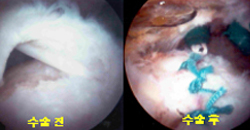

- 회전근개 파열

어깨 근육이 파열되어 통증과 함께 팔을 움직이지 못할때 관절경 수술로 빠른 회복을 얻을 수 있습니다.